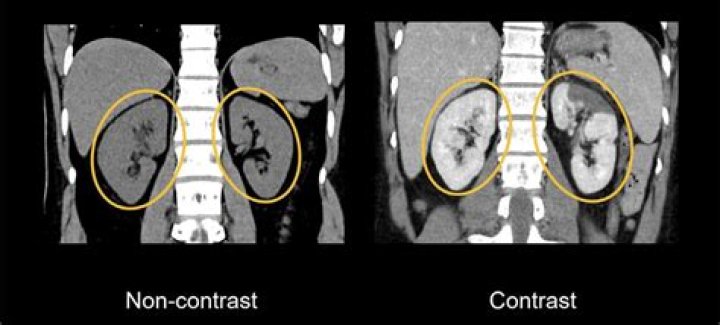

Does iv contrast obscure kidney stones?

Conclusion: Contrast-enhanced CT is highly sensitive for the detection of renal stones ≥3 mm in diameter and less sensitive for smaller stones.

Will CT with contrast show kidney stones?

Contrast-enhanced CT has a very high negative predictive value (100%) for obstructive urolithiasis and appears to accurately and safely exclude obstructing ureteral calculi for patients with acute flank pain.

Will a CT without contrast show kidney stones?

This is a study without intravenous or oral contrast, relatively low-dose (in CT terms), and has a very high sensitivity for the detection of renal and ureteric stones. CT KUB allows a rapid, contrast-free, anatomically accurate diagnosis of urolithiasis with a sensitivity of 97–98% and a specificity of 96–100%.

What type of CT scan is used for kidney stones?

Noncontrast computed tomography (NCCT) scans remain the most accurate imaging modality to detect kidney stones and to direct management.